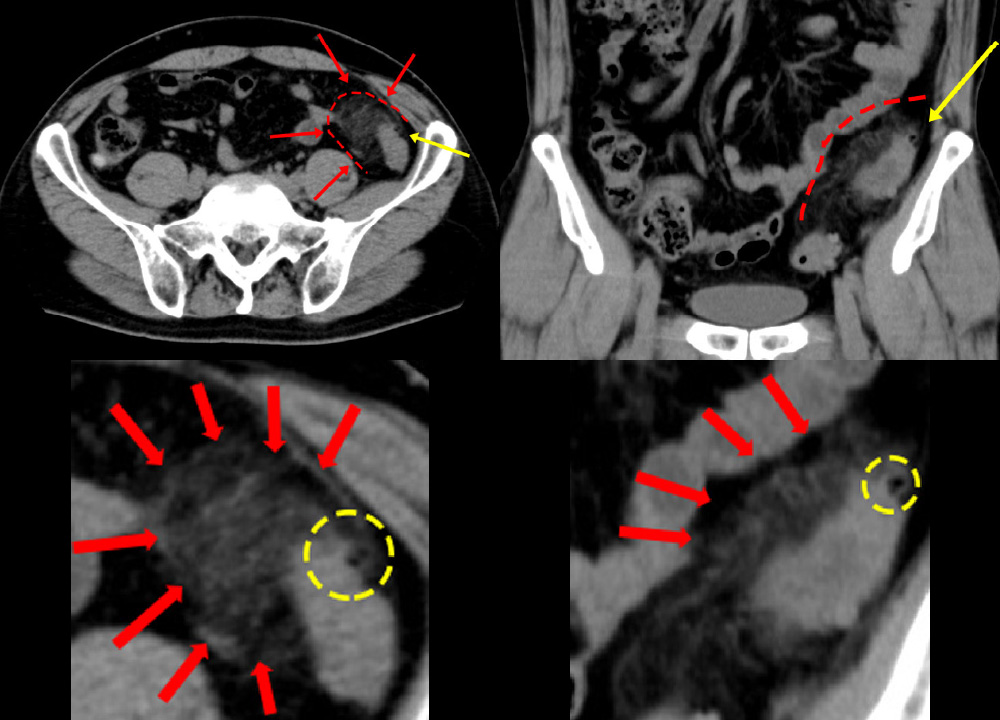

腹痛と血尿を訴えて受診。

虫垂が破れて、周囲に“うみ”をためています。炎症の波及で、膀胱へ波及→血尿が出ていました。

急性虫垂炎 急性虫垂炎 急性虫垂炎